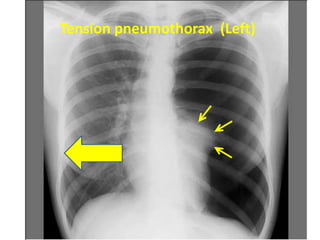

Pushed away by pleural effusion or tension pneumothorax

Tension pneumothorax

Tension pneumothorax (Left)